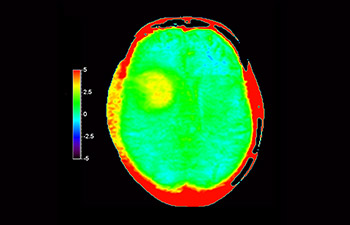

Chemical exchange saturation transfer(CEST)imagingは、MRIにおける分子イメージングの手法であり、その代表的なものにamide protontransfer(APT)imagingがある。MRIはプロトン密度と緩和時間に基づいた画像コントラストを得るのに対し、APT imagingでは可動性タンパク中のペプチド(アミド基)の濃度と交換速度に基づくコントラストが得られ、脳腫瘍の悪性度判定や放射線壊死と脳腫瘍再発との鑑別などに応用されている¹,²。

APTwイメージングでは、アミド基(NH)が対象となる。生体内のアミド基は、主にタンパク質やペプチドに含まれており、平均的には +3.5ppmの周波数に分布するとされる。アミド基のプロトンはバルク水から +3.5ppm離れた周波数帯に存在するため、交換プロトンの信号を抑制させる飽和パルスを +3.5ppmで選択的に照射する。飽和パルスによって信号が抑制されたアミド基のプロトンは、バルク水へ順次移動し、バルク水の信号を低下させる。飽和パルスの周波数を変化させながらバルク水の信号抑制を観察することで、間接的にアミド基を観察することができる(図1)。

CESTは、ごくわずかな共鳴周波数差(数100Hz)にあるプロトンを選択的に飽和させて画像化するため、静磁場B0(数十MHz)のわずかなズレでも、結果に大きな誤差が生じる。APTwイメージングでは、3D DIXON TSEシーケンスを用いB0補正を行っている。本シークエンスの利点は、3 point Dixonによる高精度のB0補正と撮像を一体化させB0不均一性に強い点と、スライスギャップなく3Dで広範囲の撮像が可能となった点である。これにより、B0不均一性に強く安定して広範囲のAPT強調像を撮像することができる⁴。